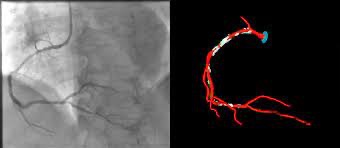

Η εικόνα δείχνει μία ενδοπρόθεση (stent) με φαρμακευτική επικάλυψη (drug-eluting stent).

Στις περισσότερες περιπτώσεις τοποθετείται stent, δηλαδή ένα λεπτό μεταλλικό πλέγμα που κρατά την αρτηρία ανοικτή.

4️⃣ Τοποθετείται stent τελευταίας γενιάς (drug-eluting)

✔ Πάντα με drug-eluting stent νέας γενιάς